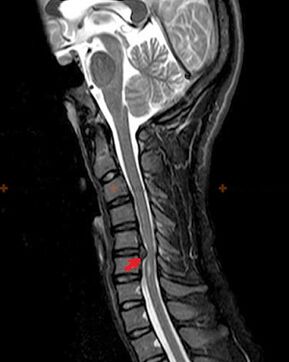

Diagnostik an Röntgenzeechen

Osteochondrose ass eng Röntgendiagnos, well eng detailléiert klinesch Bild nëmmen am Moment vun der Vergréisserung verfügbar ass, während Ännerungen an der Wirbelsäule mat komplettem subjektiv Wuelbefannen vun enger Persoun optrieden. Ouni Röntgenuntersuchung kënne mir nëmmen iwwer verdächtegt Osteochondrose schwätzen, well ähnlech Symptomer kënnen duerch aner Krankheeten verursaacht ginn (Myositis, vertebrale Neoplasmen an anerer).

Fir d’Osteochondrose ze diagnostizéieren, ginn déi folgend Fuerschungsmethoden benotzt: Radiographie (virun allem mat funktionnellen Tester), MSCT a MRI. Déi lescht Etude ass am léifsten wéinst der Tatsaach, datt et et erméiglecht, den Zoustand vun den intervertebrale Strukturen ganz kloer ze visualiséieren.

Röntgenzeechen vun Osteochondrose enthalen déi folgend Verännerungen an der Wirbelsäule:

- Reduzéiert Héicht vun intervertebral Discs.

- Präsenz vu marginale Knochenwachstums.

- Violatioun vun der Plaz vun der Wirbelen relativ zu all aner.

- Deformatiounen vun vertebrale Kierper a Bunnen, etc.

D’Präsenz vun den uewe beschriwwenen Ännerungen, wéi och d’Verännerungen an der Struktur vun der intervertebral Disc, déi duerch MSCT a MRI festgestallt gëtt, déngen als zouverlässeg Schëlder, déi d’Präsenz vun Osteochondrose bestätegt.